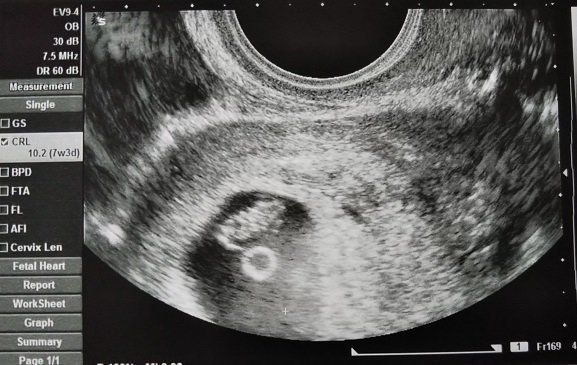

妊娠7週目のエコー写真 赤ちゃんの姿が!心音も聞かせてもらい、幸せを実感

妊娠7週目。初診で言われた2週間後の検診の日…。ドキドキしながらの受診でしたが、診察してもらうと、赤ちゃんの袋、胎嚢の中に赤ちゃんの姿が見えました!心音を聞かせてもらったときには、涙が出てきました。帰りには母子手帳をもらいに行って、うれしさいっぱいでした。